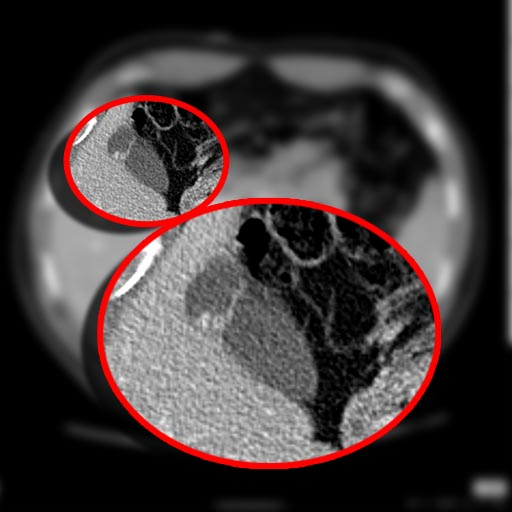

In medicine, a Phrygian cap is the folded portion of some gallbladders that resembles the Phrygian cap (a soft conical cap with the top pulled forward, associated in antiquity with the inhabitants of Phrygia, a region of central Anatolia). It is a normal anatomical variant seen in 1-6% of patients. It is caused by a fold in the gallbladder where the gallbladder fundus joins the gallbladder body. Apart from the chance of being mistaken for stones on a sonogram, it has no other medical implications nor does it predispose one to other diseases.[citation needed] However, due to potential decrease in bile flow, it may warrant a preventive removal of the gallbladder.[citation needed]